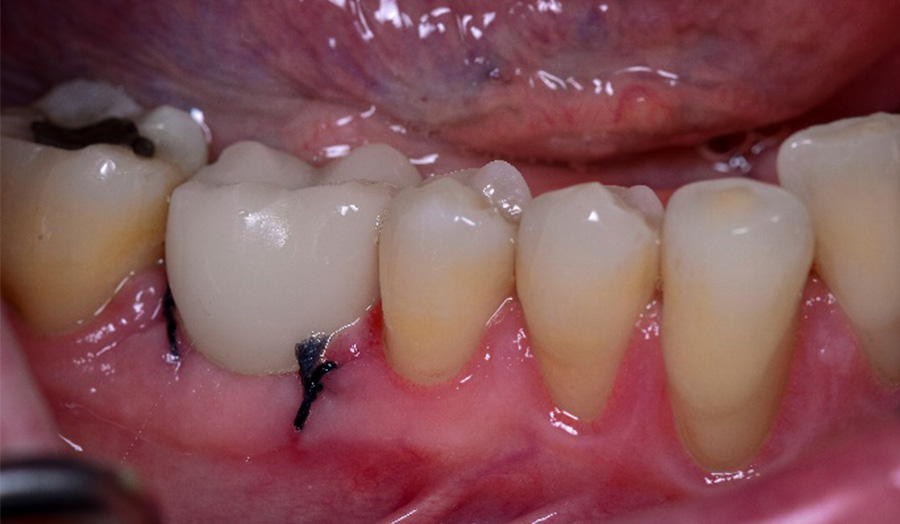

A 62-year-old male presented himself to my practice with a fractured non-restorable tooth #10. We planned a single implant with a surgical guide and a temporary bridge, both manufactured with Primeprint. The surgery was completed in 20 minutes, and it took us 10 minutes to bond the temporary bridge.

Before: Initial situation with a fractured non-restorable tooth #10

Usage: Placing the 3D-printed surgical guide with Primeprint Guide material with excellent fit